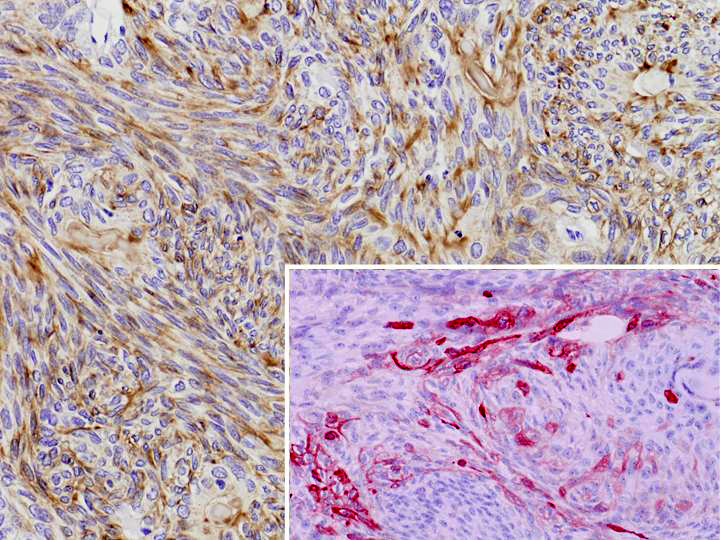

主体をなす紡錘形細胞および類円形細胞は広範にEMA陽性,一部involucrin陽性を呈し(inset),上皮筋上皮癌の化生性変化から生じたものと解された. |